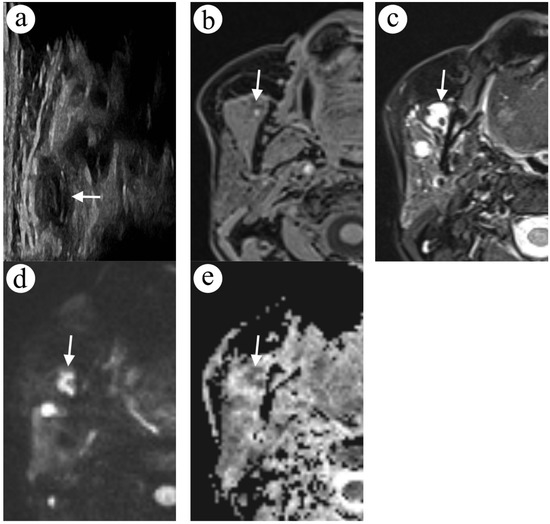

2.4. Case 4